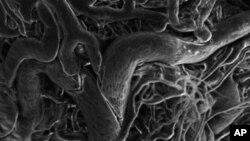

Out-of-control blood vessels associated with retinopathy as imaged by a scanning electron microscope.

Retinopathy of prematurity affecting infants, diabetic retinopathy in adults and age-related macular degeneration in older people, all involve abnormal blood vessel growth in the retina that interferes with vision.